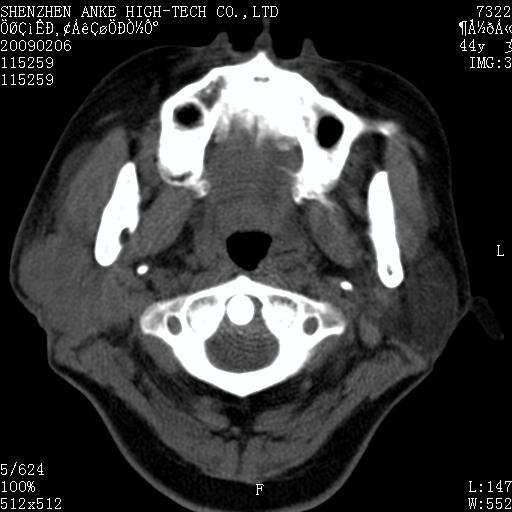

标题: CT17977:女,44岁,右侧颌部包块1年,右侧面瘫2月。 [打印本页]

患者:女,44岁,右侧颌部包块1年,右侧面瘫2月。

考虑右侧腮腺混合瘤可能性大

考虑右侧腮腺混合瘤。

考虑右侧腮腺混合瘤。年轮样伪影考虑机器问题!

考虑右侧腮腺混合瘤;不排除腮腺癌。

右侧腮腺肿瘤,良恶性难定。